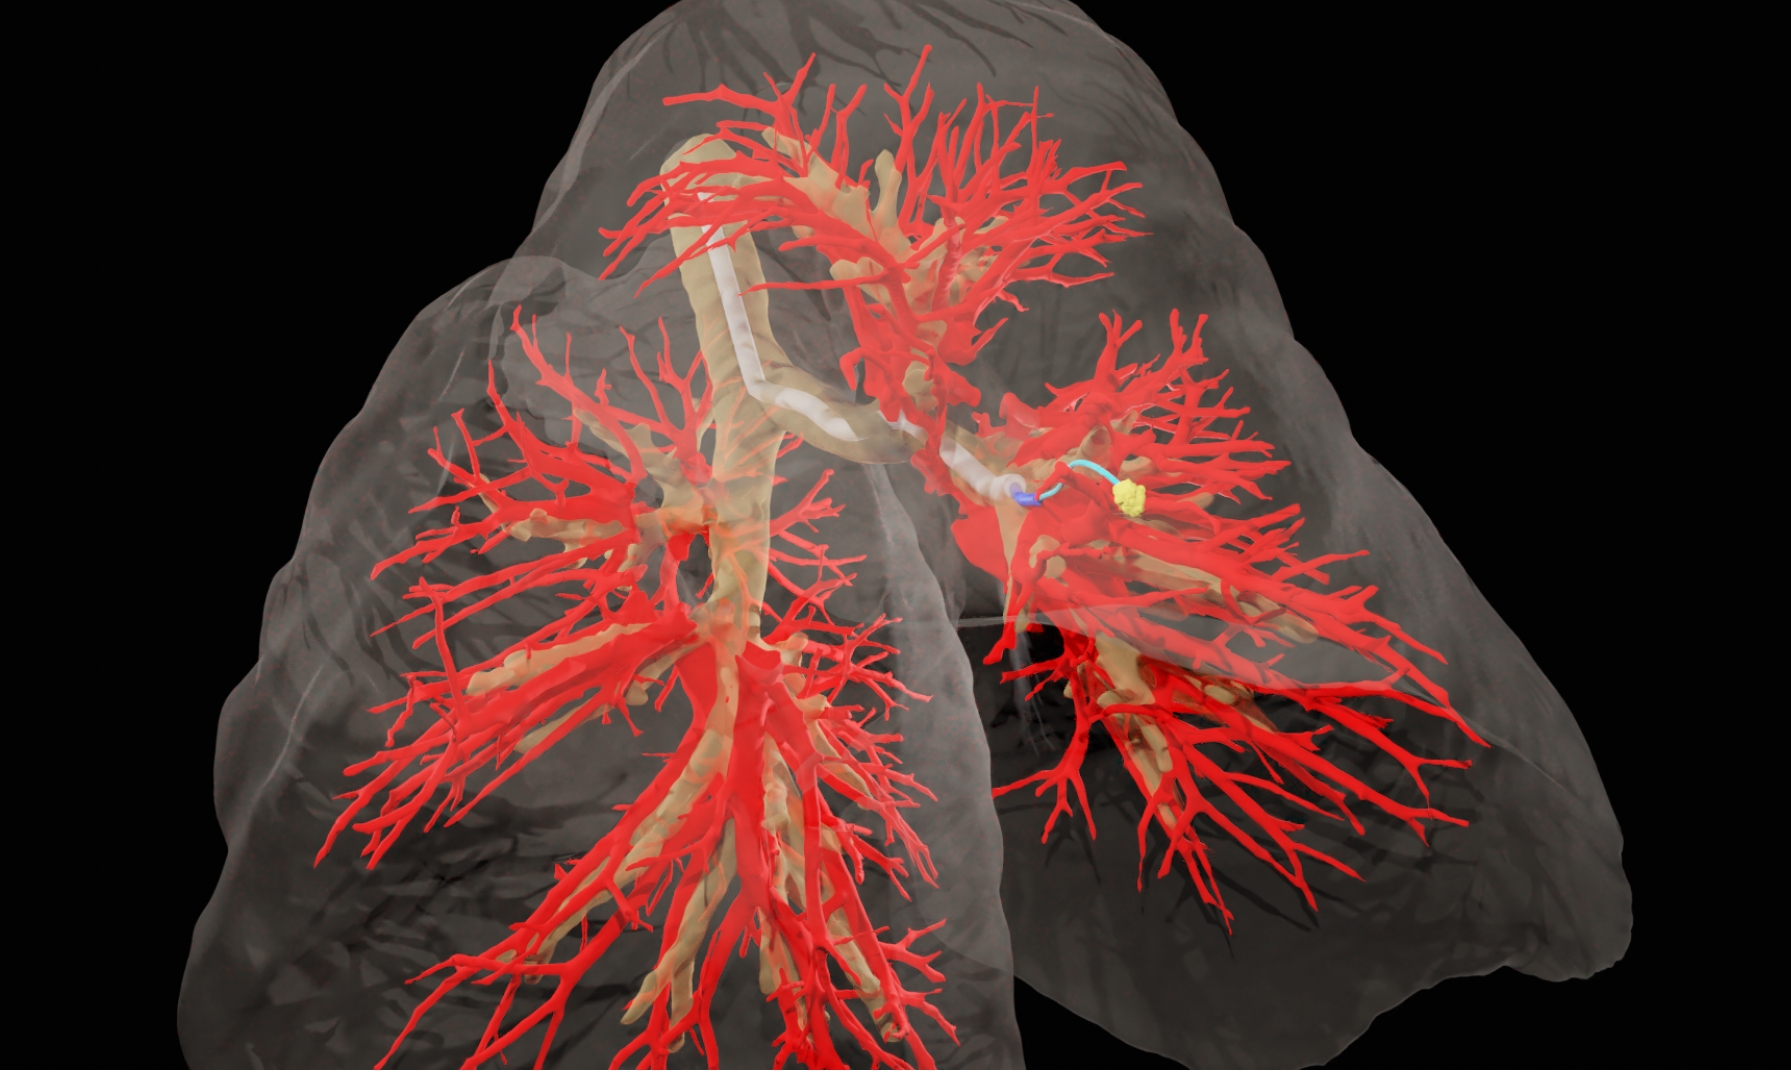

可操纵针必须绕过解剖障碍才能到达肺部结节。为了穿过组织,针需要知道它要去哪里。研究小组利用受试者胸腔的CT扫描来创建肺部的三维模型,包括气道、血管和选定的目标。借助这个3D模型,他们的人工智能驱动软件可以指示针自动从一个点移动到另一个点,同时避开重要的结构。